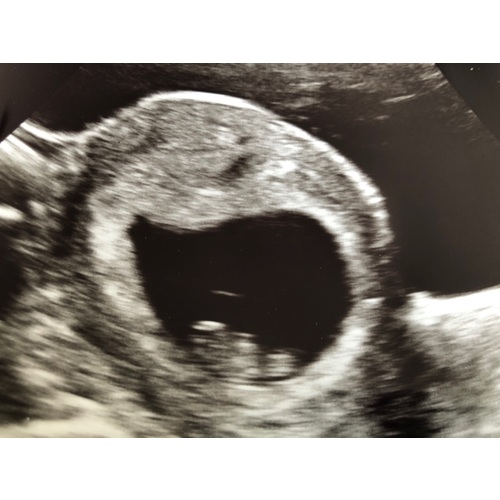

Uitwendig was er wel wat te zien, maar nog niet heel duidelijk.

Dit is de inwendige echo met 8 weken. Met een mooi sterk hartje.

Hartje kan je niet horen met 8 weken, wel kan je het zien kloppen. En dat is net zo magische🥰